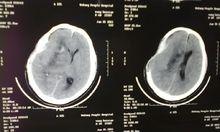

該過程被列為緊急情況下,頭顱內的壓力(顱內壓),通常在大腦內的出血或它的覆蓋,增加了危險的程度。

骨瓣遭受永久性的腦損傷出血,感染,或顱內壓增高的可能認知能力下降。他們可能無法執行任務,他們在手術前。在某些情況下,減值可以嚴重到需要永久性殘疾。通過枕下骨瓣取出與聽神經瘤的個人可能會遇到永久性的聽力損失和喪失能力的平衡問題。

通過骨瓣減壓手術治療的方法進行手術的併發症包括出血,腫脹的腦組織,導致神經細胞的損傷,傷口感染,顱神經損害,泄漏的液體覆蓋的大腦(腦脊液),術後頭痛。空氣進入靜脈(靜脈空氣栓塞),可以形成一個氣泡,阻止了小血管,導致中風。